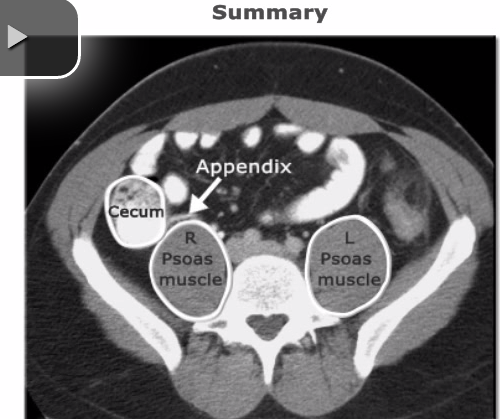

Describe how to visualize appendix on axial CT slice of the abdomen

Locate appendix btwn the cecum (will be filled w/ contrast and gas) and the right psoas muscle

-joins the cecum btwn 2-6 oclock